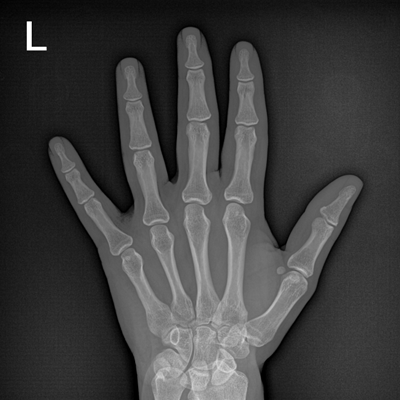

用于影像科、急診室、病房、ICU、手術(shù)室等多場景應(yīng)用。

● 數(shù)字化無線平板成像,操作簡便,成像質(zhì)量高